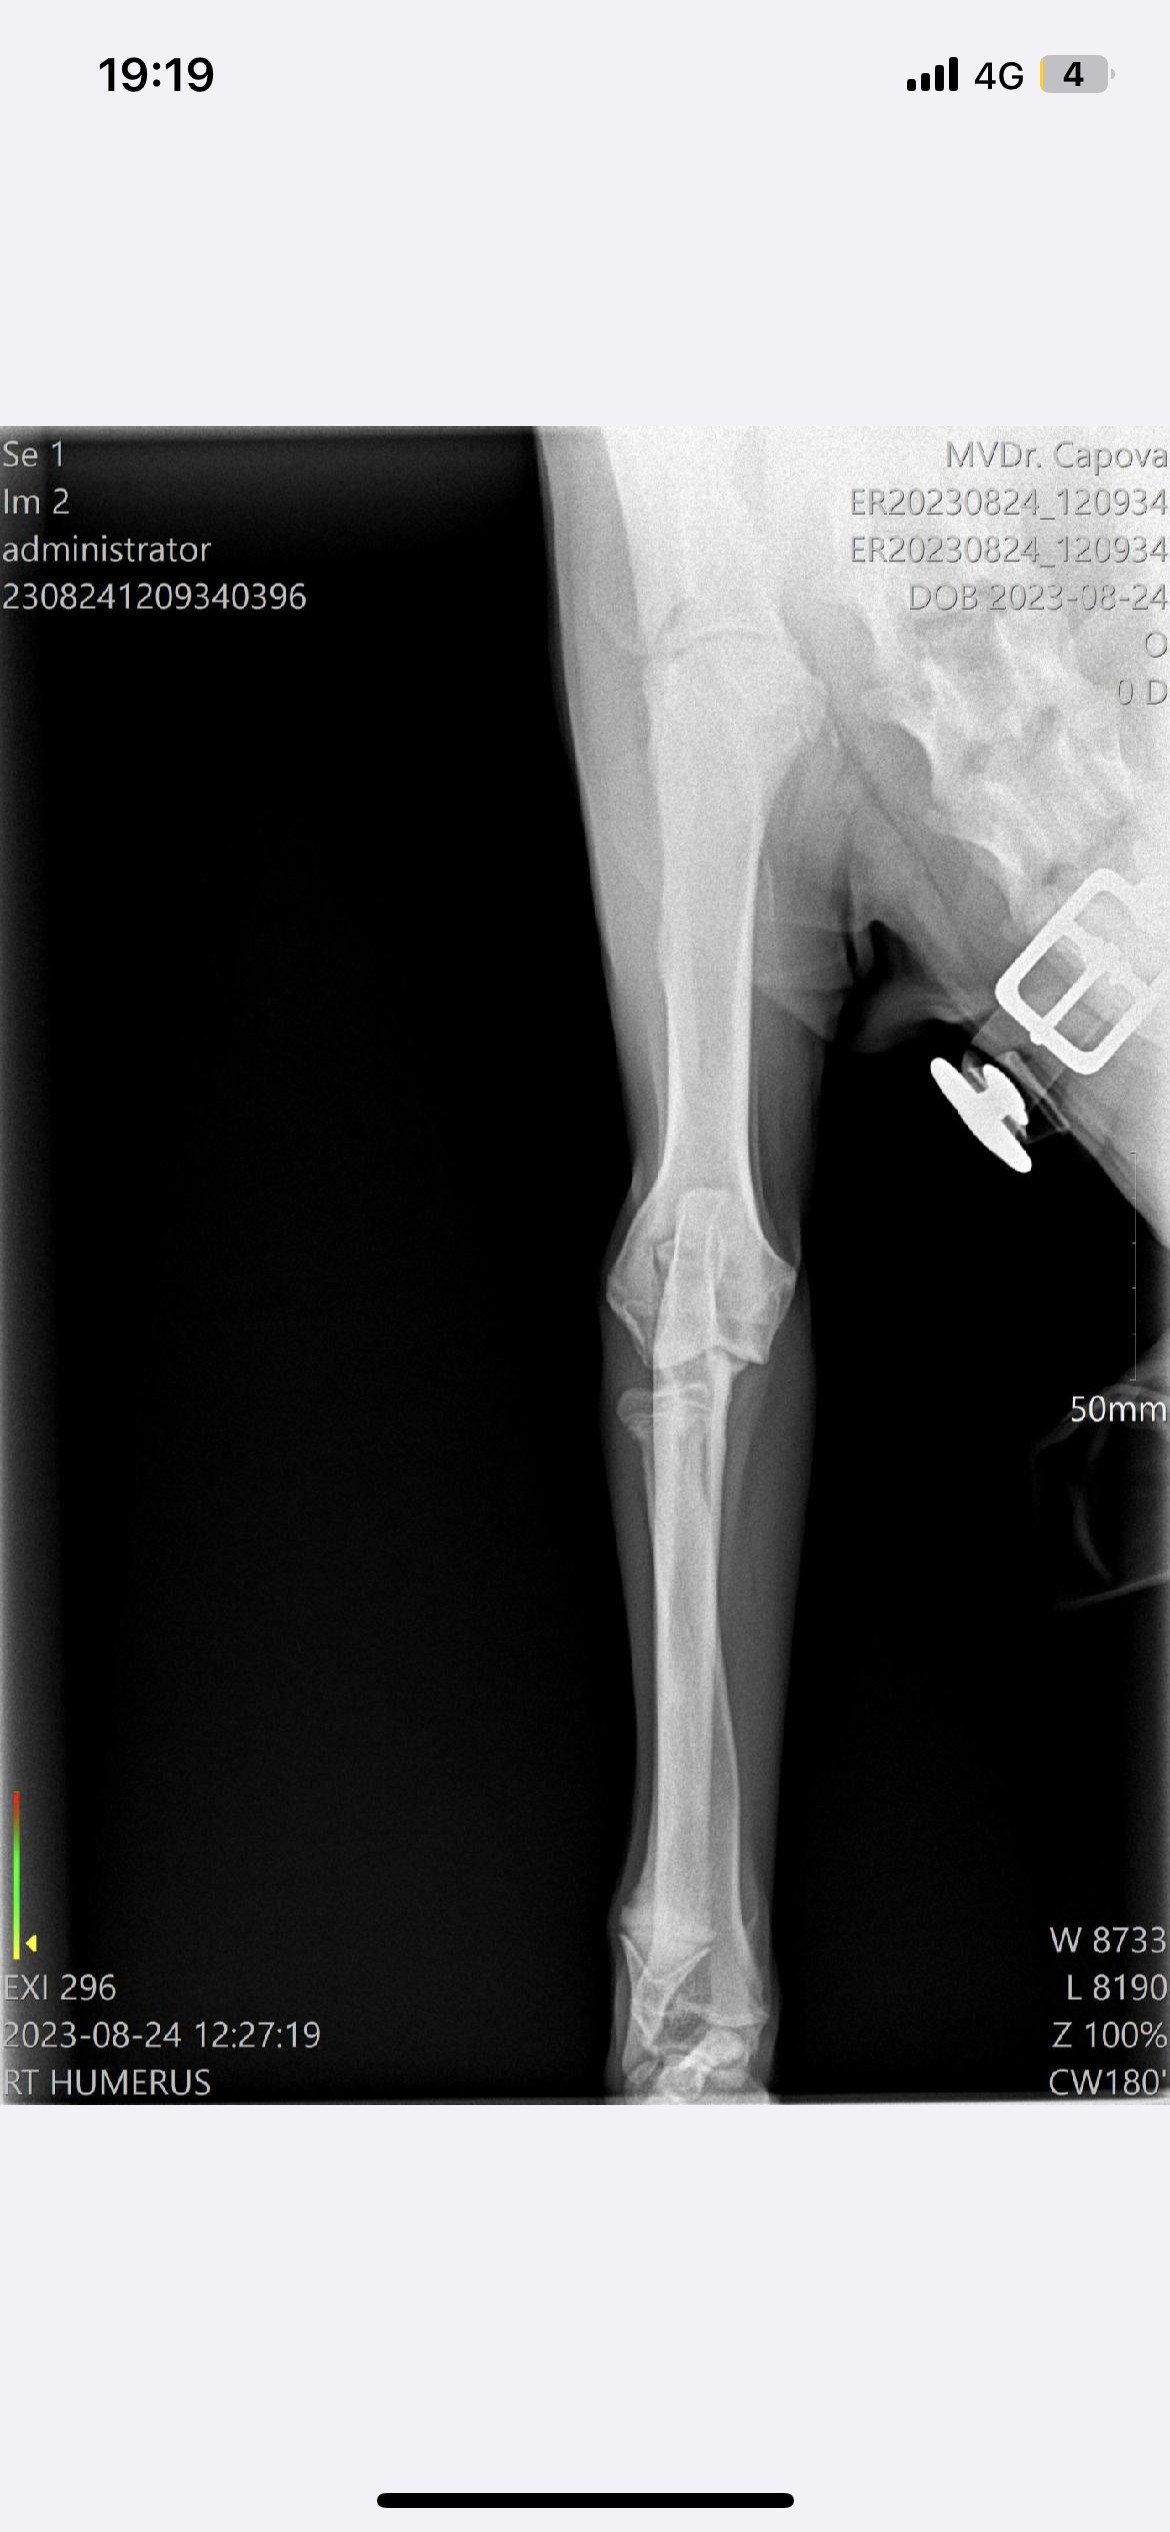

Operace a léčba pro Barlettku

Představení sbírky

Komu pomůžeme?

Na co konkrétně budou peníze z této sbírky použity?